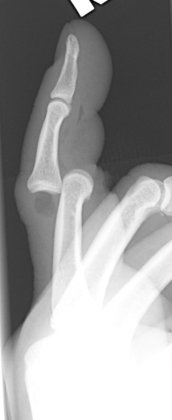

Return to Coach' s Finger